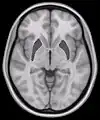

Horizontal slice of MRI-image showing the putamen. The other nuclei of the basal ganglia (caudate nucleus and globus pallidus) can be seen as well.